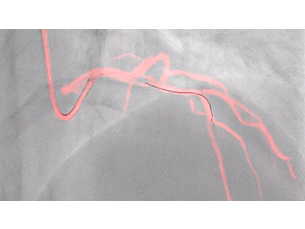

Our imaging technology ClarityIQ, combines advanced, real-time image noise reduction algorithms with state-of-the-art hardware. Together, they form a flexible digital imaging pipeline designed to perform individual image processing algorithms more efficiently. This unlocks superb visualization and significant dose reduction capabilities for healthcare facilities. ClarityIQ is available as an option on Azurion systems.